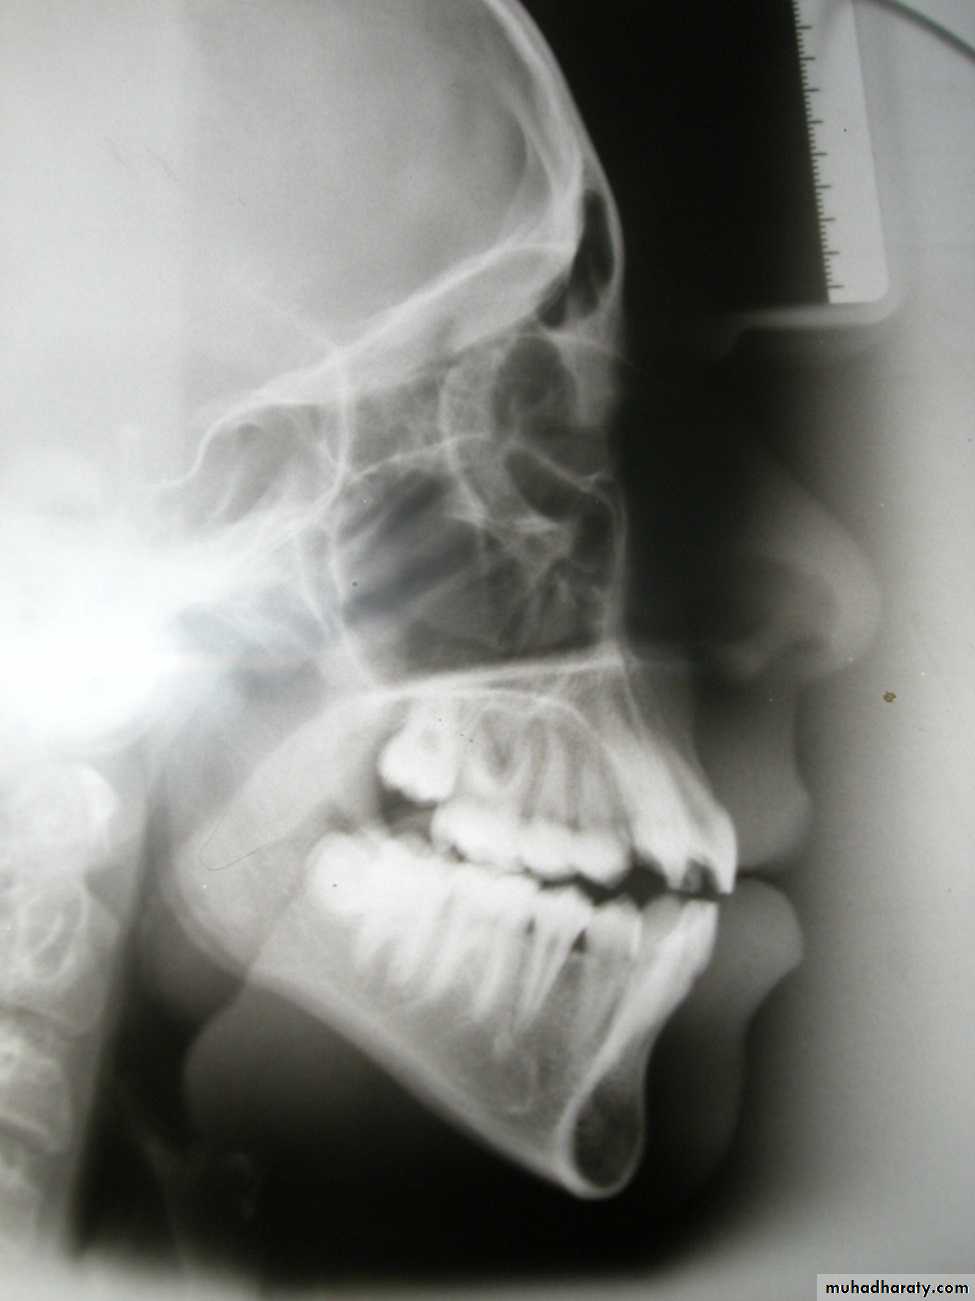

Cephalometric assessment

Cephalometric lines of reference

1. True horizontal:

Can be identified when the patient’s head is in the natural postural position, this line is differ from one person to other.

2. Frankfort plane:

Po - Or